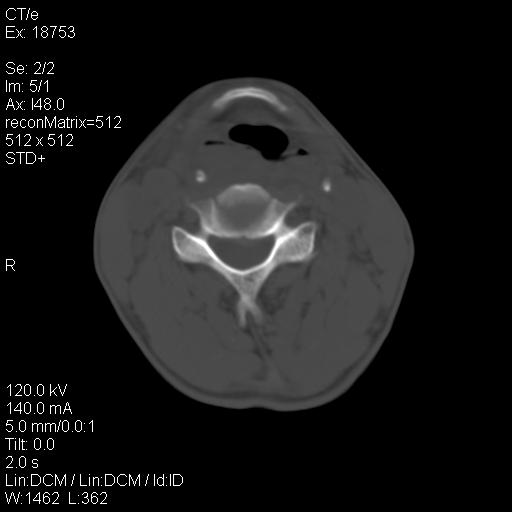

标题: CT21693:男 58岁 右侧咽部疼她2天余 PE:右侧扁桃体肿大 压痛 [打印本页]

标题: CT21693:男 58岁 右侧咽部疼她2天余 PE:右侧扁桃体肿大 压痛

右化脓性扁桃体炎症伴咽后壁脓肿形成.